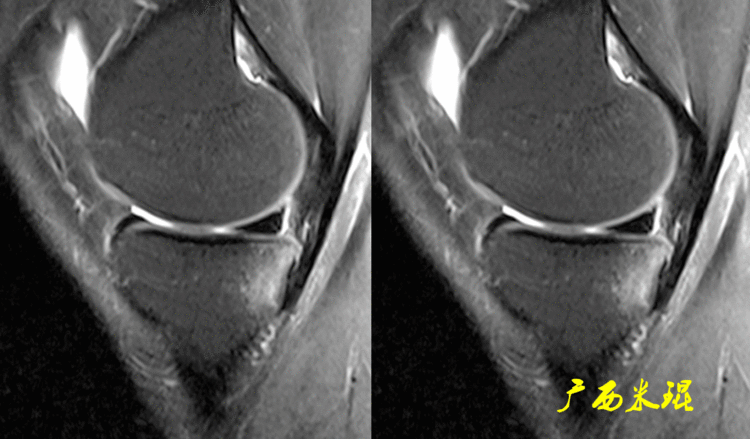

下面矢状位MR是外侧半月板后角部分切除手术后,片上我们发现半月板后角部分缺失,半月板信号正常(因为手术前半月板没有退变)。

下面矢状位MR是内侧半月板后角水平撕裂部分切除手术后,半月板后角部分缺失,信号仍然不正常(因为手术前半月板已经有退变),真正的情况是关节镜下半月板外观是正常的,MR上看见的高信号影是半月板退变的Ⅱ级信号所致,由于手术切除面达退变的层面,MR上容易误诊为Ⅲ级信号。

下面矢状位MR是内侧半月板后角纵形撕裂缝合手术后,半月板外观完整,无分离,缝合处小片状稍高信号,这个高信号几乎不可能消失(半月板损伤痕迹永远存在)。

内侧半月板后角纵形撕裂缝合手术后,半月板外观完整,无分离,缝合处的线状稍高信号一般情况下也永久存在。

如同下面这张MR,左侧图像为手术前的,右侧图像为手术后的,术后病人疼痛等症状仍然存在,复查MR见外侧半月板前角分层,半月板前角的处理是有一定难度的,有经验的医生会考虑可能是手术者对前角的处理不够熟悉,没有通过另外的办法处理半月板前角的水平裂,不过也只能是猜测而已。所以,对于半月板术后的评估,症状的消失比MR重要!